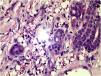

HistopatologíaLa biopsia evidenció la presencia de granulomas con vasculitis de vasos pequeños. La tinción de Fite-Faraco reveló la presencia de numerosos bacilos ácido resistentes (AFB) en los filetes nerviosos y vasos (fig. 3).

En nuestro paciente, los hallazgos histopatológicos mostraron principalmente vasodilatación y engrosamiento de los vasos de la pared del plexo superficial y profundo de la dermis, proliferación de células endoteliales y, en ocasiones, coágulos intraluminales conducentes a necrosis dermoepidérmica. La tinción de Fite-Faraco fue positiva para la presencia de bacilos en el interior y alrededor de los vasos, y en el endotelio de la pared vascular.